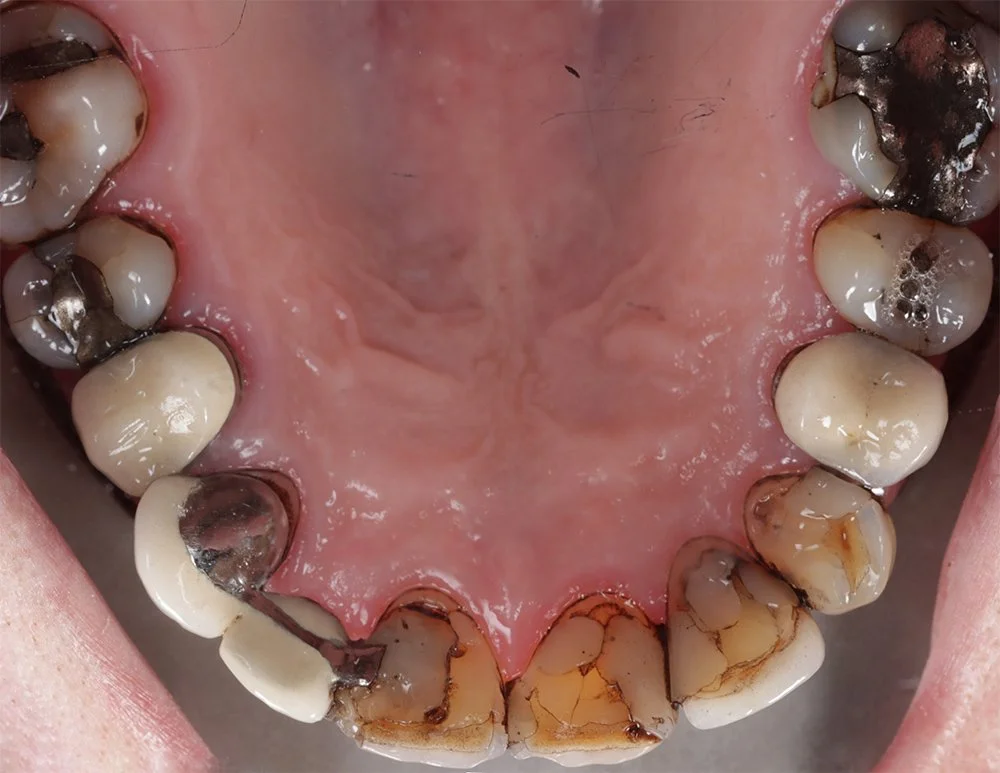

Before and After Treatment